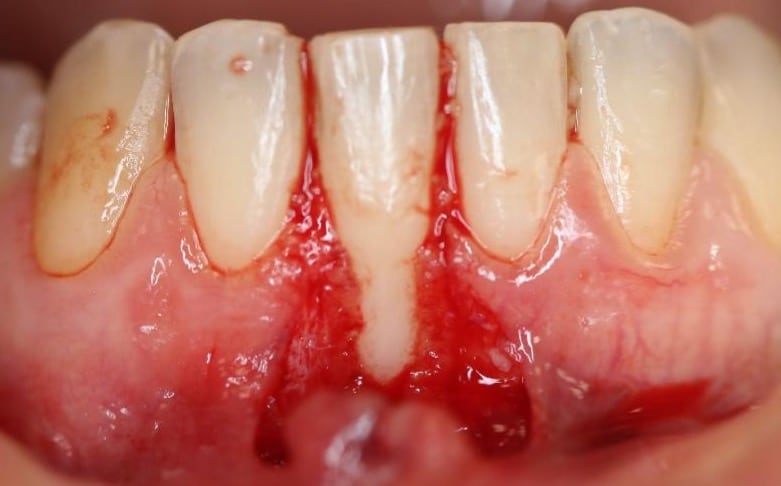

Coronally Advanced Flap with connective tissue graft

This method is commonly used to achieve total root coverage in isolated and multiple recession sites. This method requires harvesting a connective tissue graft from the palate. This graft is then sutured onto the defect, and it is subsequently covered by a coronally advanced flap.

Figure 2. Surgical management of lower anterior recession using a coronally advanced flap and subepithelial connective tissue graft.